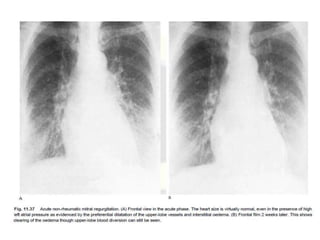

• In the acute phase, the heart size is likely to

remain normal even in the presence of a high

left atrial pressure.

• This high pressure in the acute phase often

leads to the formation of acute pulmonary

edema